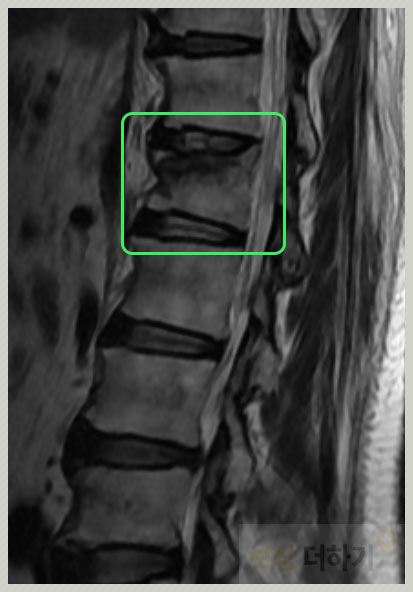

척추 성형술

대부분은 보존적인 치료를 선택합니다. 신경 손상이 없고 척추뼈의 높이 감소가 심하지 않고 구조적으로 안정적이라면 가능합니다. 하지만 다음과 같은 때에는 척추 성형술을 고려하게 됩니다. · 보존적 방법으로 효과가 없음 · 심각한 통증 · 척추뼈의 추가 붕괴 위험 · 척추의 변형 (높이 감소, 구조적 문제) · 골다공증성

단순 척추 성형술 : 골절된 뼈에 의료용 시멘트를 주사 풍선 척추 성형술 : 시멘트 주입 전 작은 풍선을 넣어 눌린 뼈의 높이를 복원 후 시멘트로 고정

처음에는 보존적인 치료를 하셨지만 증상이 악화되면서 통증이 심해졌고, 약 2년 뒤에는 척추 성형술을 시행받았습니다. 그 후에도 통증이 심해질 때마다 입원을 하며 치료를 하셨다고 해요. 그러다 후유장해 보상에 대해 알게 되셨고 저희 「보상 더하기」에 문의주신 때는 성형술 하신지 약 1년이 지난 시점이었습니다.